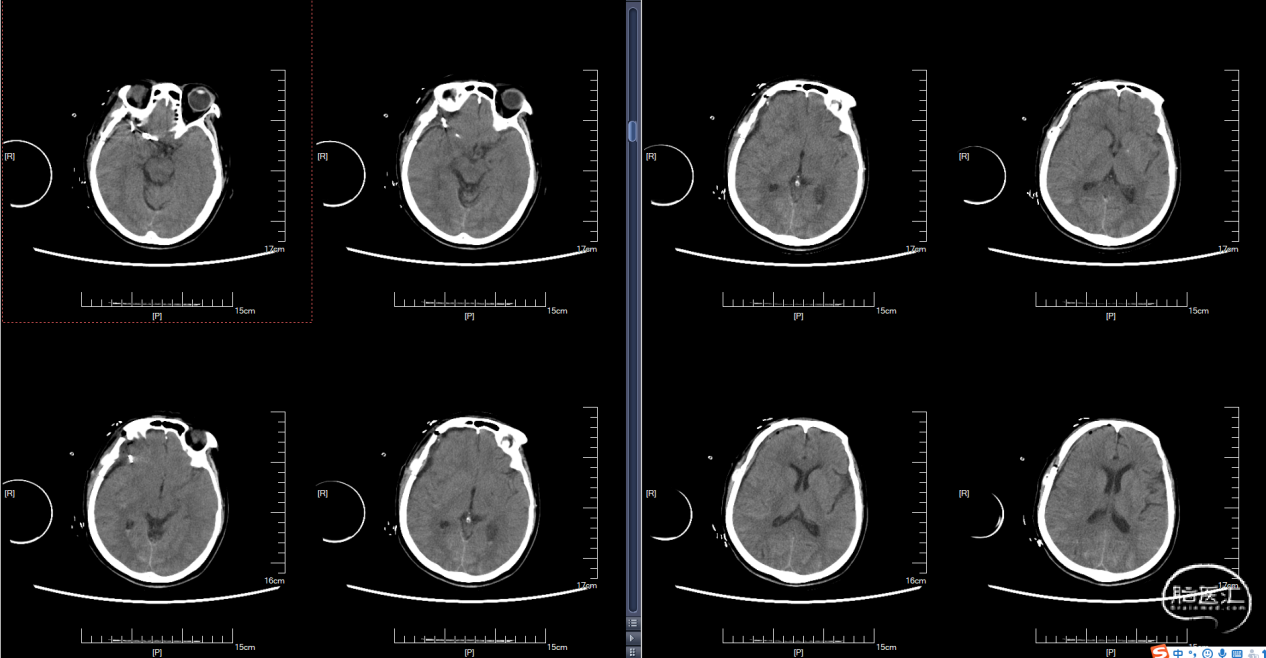

术后复查CT:

术后10天复查CTA: